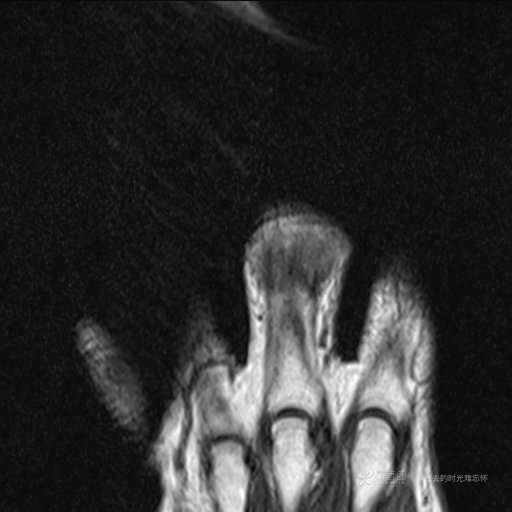

患者性别:女

患者年龄:59岁

主诉: 手指肿胀2年,其间明显肿胀,抗炎后肿胀减轻,近几日肿胀疼痛加重。

T2及T2压脂